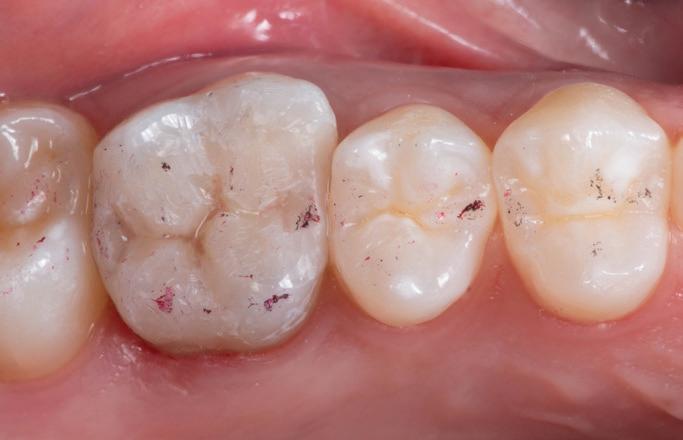

At 21 months following retreatment, the patient and parent were satisfied with the final treatment outcome, as all complaints were resolved. The follow-up radiograph showed an

improved periapical index score of 1, reduced from the immediate postoperative score of 3 (Fig 10).

Fig 10. Radiograph 21 months after retreatment with coronal pulpotomy, revealing resolution of the periapical lesion.